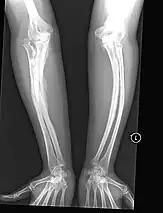

The main symptom of osteogenesis imperfecta is fragile, low mineral density bones; all types of OI have some bone involvement.[5] In moderate and especially severe OI, the long bones may be bowed, sometimes extremely so.[28] The weakness of the bones causes them to fracture easily—a study at the Endocrine Unit at the National Institute of Child Health in Karachi, Pakistan found an average of 5.8 fractures per year in untreated children.[29] Fractures typically occur much less after puberty, but begin to increase again in women after menopause and in men between the ages of 60 and 80.[1]: 486

- Type V – Having the same clinical features as type IV, it can be clinically distinguished by observing a "mesh-like" appearance to a bone biopsy under a microscope. Type V can be further distinguished from other types of OI by the "V triad": an opaque band (visible on X-ray) adjacent to the growth plates; hypertrophic calluses (abnormally large masses of bony repair tissue) which form at fracture sites during the healing process; and calcification of the interosseous membrane of the forearm,[50] which may make it difficult to turn the wrist.[1]: 429 Other features of this condition may include pulled elbow, and, as in other types of OI, long bone bowing and hearing loss.[64] Cases of this type are caused by mutations in the IFITM5 gene on chromosome 11p15.5.[64][49] The separation of type V from type IV OI, its clinical type, was initially suggested even before its genetic cause was known, by Glorieux et al. in 2000.[50][65] Type V is relatively common compared to other genetically defined types of OI—4% of OI patients at the genetics department of the Brazilian Hospital de Clínicas de Porto Alegre were found to have it.[66]

Diagnosis is typically based on medical imaging, including plain X-rays, and symptoms. In severe OI, signs on medical imaging include abnormalities in all extremities and in the spine.[97] As X-rays are often insensitive to the comparatively smaller bone density loss associated with type I OI, DEXA scans may be needed.[5]: 1514

In those with type III OI who had undergone rodding surgery, 79.5% had the femurs and tibias of both legs rodded.[25]: Table I The most common form of rods used are intramedullary (IM) rods, some of which, such as the Fassier–Duval IM rod, are telescoping, meaning that they are designed to grow as the child grows, in an attempt to avoid the necessity of revision surgeries.[118] Telescoping IM rods are widely used,[119] and the common Fassier–Duval IM rod is designed to be used to rod the femur, tibia, and humerus.[120]: 1 The surgery involves breaking the long bones in between one and three (or more)[119]: Figure 4 places, then fixing the rod alongside the bone to keep it straight.[120]: 11

While telescoping IM rods are intended to grow along with both the femur and tibia in developing children; surgeons have a preference to use non-telescoping IM rods, such as Rush rods, in the tibia, which grows less comparatively—the JB&JS review found that while 69.7% of femurs were treated with telescoping IM rods, only 36.9% of tibiae were.[25]: Table IV